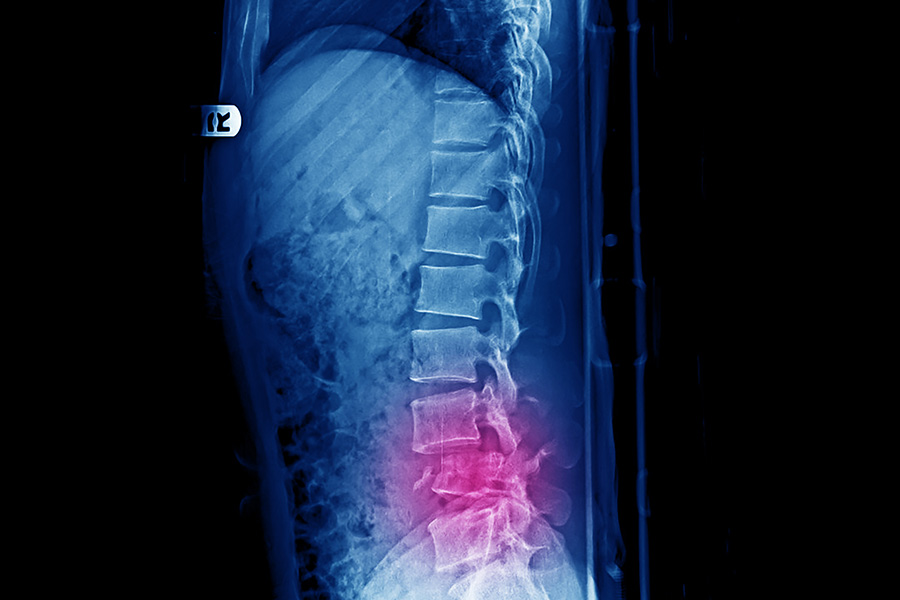

Vertebral Compression Fracture (VCF)

What Is a Vertebral Compression Fracture?

A vertebral compression fracture happens when one of the bones in your spine collapses.

This can result from osteoporosis, other bone-weakening conditions, trauma, or a combination of factors.

Sometimes they happen after a fall or accident, but in weakened bone, even everyday movements — like bending forward, lifting, or coughing — can cause a fracture.